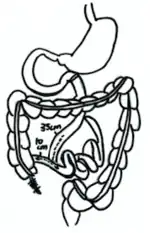

Jejunocolic bypass

First performed in 1963, the jejunocolic bypass is regarded as the first type of intestinal bypass surgery. This surgery anastomoses the proximal duodenum to the transverse colon (a part of the large intestine). The surgery, nevertheless, turned out to be a huge failure as patients suffered from severe electrolyte imbalance and metabolic disturbance after it.[5]